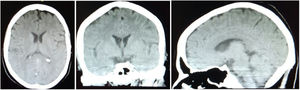

Se realizaron exámenes para descartar organicidad. Una tomografía computarizada (TC) simple de cráneo no evidenció lesiones estructurales (figura). Los estudios paraclínicos séricos mostraban unas adecuadas funciones tiroidea, renal y hepática, equilibrio hidroelectrolítico y hemograma dentro de normalidad (tabla 1), por lo que se descartó cualquier proceso sistémico que pudiera estar asociado con este cuadro.